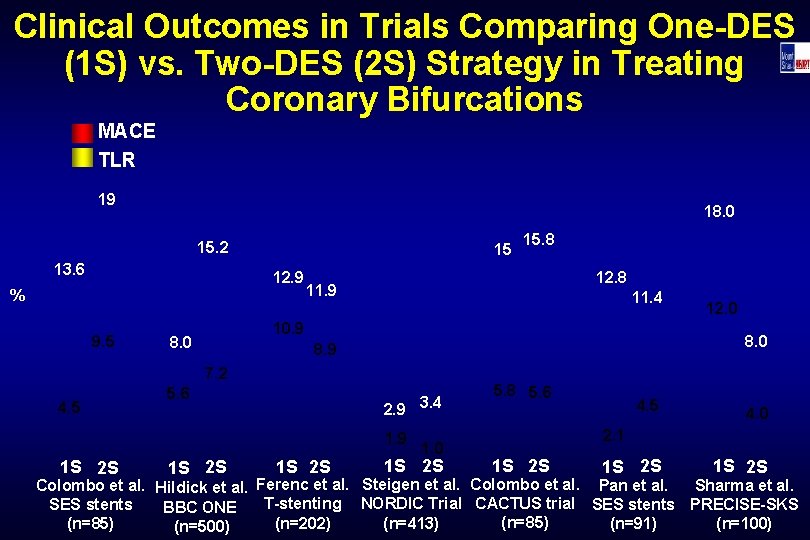

Clinical Outcomes in Trials Comparing One-DES (1 S) vs. Two-DES (2 S) Strategy in Treating Coronary Bifurcations MACE TLR 19 18. 0 15. 2 13. 6 15 12. 9 % 9. 5 12. 8 11. 9 11. 4 10. 9 8. 0 5. 6 2. 9 3. 4 1. 9 1 S 2 S 12. 0 8. 9 7. 2 4. 5 15. 8 1. 0 1 S 2 S 5. 8 5. 6 4. 5 4. 0 2. 1 1 S 2 S Colombo et al. Hildick et al. Ferenc et al. Steigen et al. Colombo et al. Pan et al. Sharma et al. T-stenting NORDIC Trial CACTUS trial SES stents PRECISE-SKS SES stents BBC ONE (n=85) (n=202) (n=413) (n=91) (n=85) (n=100) (n=500)